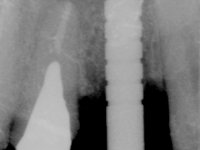

Patient male, 60 years old, non-smoker. After imaging and clinical examination, it was found that the patient had teeth 2.1 and 2.2 with extensive acrylic restorations, with screwed intra radicular posts and very poor endodontic treatments. Tooth 2.2 had an extensive apical lesion, the post had been placed on a false route and had mobility. Tooth 1.1 had an extensive resine restoration and tooth 1.2 presented a mesial restoration, also in composite resin, Class III type. The antero-superior sector was vestibularized, as consequence of a loss of vertical occlusion dimension associated with posterior edentulism. The patient showed reasonable periodontal health and satisfactory oral hygiene.

Endodontic treatments were performed and a metalic non screwed intra radicular post was placed on tooth 1.1. An alginate impression was made for laboratory confection of a reinforced acrylic provisional bridge, with teeth 1.1 and 2.2 as abutments and 2.2 as a pontic. After preparation of tooth 1.1 and root preparation of 2.1, the bridge was relined in mouth with self-polymerizable acrylic using a metal post for further retaining the prepared root canal on 2.1. Tooth 2.2 was cut at the gingival level to function as support. In the same session, the impression of the root canal of the 2.1 was made for the laboratory confection of a cast post and core. A double mixture technique with plastic tutor was used after previous canal vaseline with endodontic file and cotton. The provisional bridge was provisionally cemented and the cast post and core was made in the laboratory. Cast post and core cementation was made with resin-reinforced glass ionomer cement and the provisional bridge had to be readjusted to the new situation by removing the post at the site of 2.1. After careful surgical planning, a dental implant was placed, simultaneously with extraction of the root of tooth 2.2. The provisional bridge was placed by resting on the healing screw placed in the implant. The respected osteointegration period was 12 weeks, during which the provisional bridge was relined twice. After complete maturation of hard and soft tissues, definitive impressions were made. The gingival retraction technique was applied with an impregnated retraction cord and impression was performed using double mixture, open tray impression technique. A custom precious metal abutment implant was prepared in the lab, along with 3 metal caps to be used as infrastructures for the metal ceramic crowns. Particular care was taken in the confection of the cervical finishing line of the implant abutment, in order to follow the soft tissues emergence profile. Proof of infrastructures was done in the mouth being evaluated clinically and imagiologically. Collection of color information was done by the ceramist at the office. Ceramic was applied in the laboratory and the finished work was placed in the mouth after approval by the patient. Definitive cementation was made with resin-reinforced glass ionomer cement, and the first crown to be cemented was that of the implant, to facilitate removal of the excess.